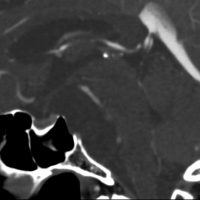

骨をみているCTです。鞍背からsphenooccipital synchondrosisまでの斜台骨皮質が失われています。かなり特徴的な所見です。